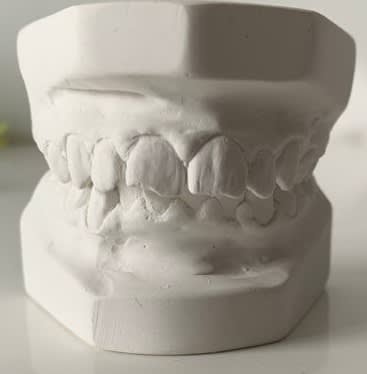

Je souhaiterais avoir vos avis sur le traitement orthodontique de ce cas : Classe II division 1 importante avec biproalvéolie.

Traiteriez vous ce petit patient de 13 ans et 1/2 avec d'emblée 4 extractions de prémolaires (14 24 35 45) et mécanique de classe II par élastiques ?

Ou commenceriez vous d'abord par corriger la classe II avec par exemple un carriere motion (pour une avancée mandibulaire - patient encore en croissance en vue de la maturation osseuse cervicale- et surtout un recul maxillaire) puis les extractions à réévaluer pour la biproalvéolie ?

Le profil du jeune homme me semble incompatible avec un traitement de camouflage par extraction de premolaires, ca donnerait un profil vraiment pas joli. Ensuite, le carriere motion donne principalement un recul de l'arcade maxillaire et une derive mesiale de l'arcade mandibulaire, rien de tout ça ne donnera un visage esthétiquement satisfaisant ni ne repondra au problème du patient, ca ne fera encore une fois que camoufler la situation. À la limite, je comprendrais mieux qu'on reflechisse à une orthopedie d'avancee mandibulaire, mais vue la proalveolie mandibulaire et vue l'importance de la retromandibulie, ca ne me parait pas raisonnable.

Alors, je suis d'accord que des avulsions seraient déléteres sur le profil du patient là.

Dans un cas comme celui là des avulsions plutot de classe 3 : les 5 en haut et les 4 en bas.